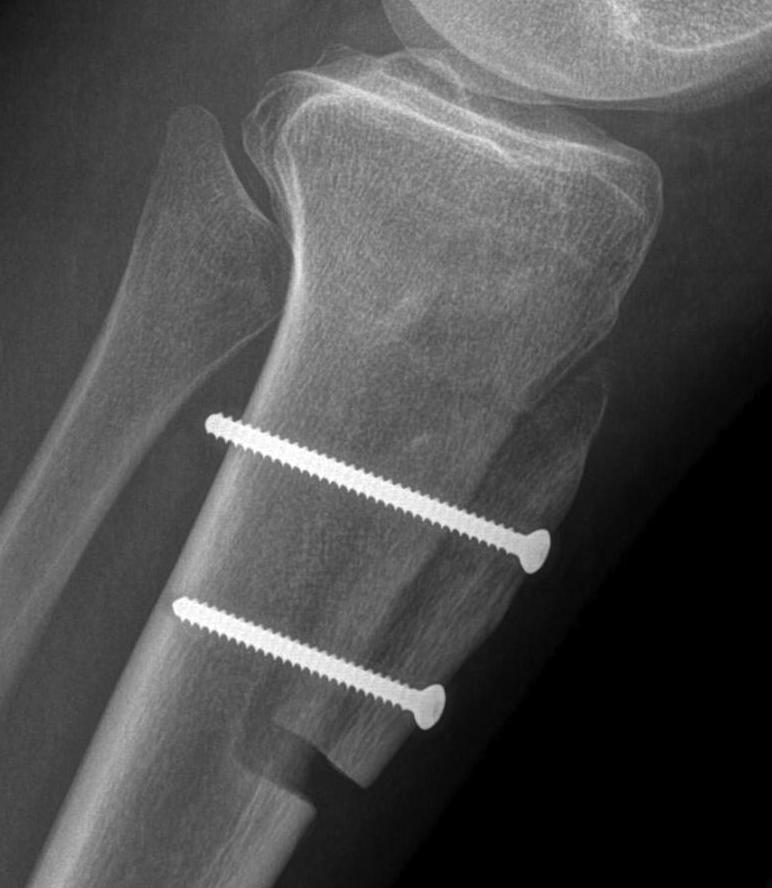

Fulkerson

Technique

Oblique osteotomy 45˚

- enables antero-medial transfer of tibial tuberosity

- unloads the lateral facet simultaneously